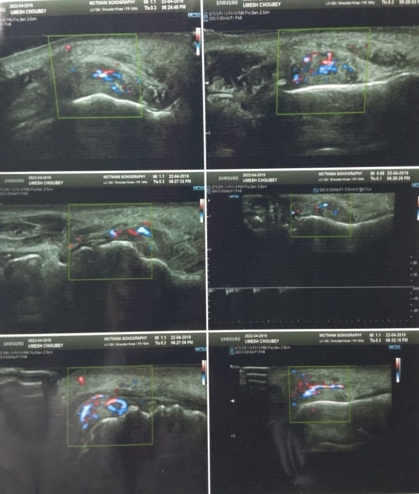

We made a differential diagnosis of Periperal ossifying fibroma, haemangioma, extravasation mucocele, giant cell epulis, soft tissue fibroma. To narrow down our diagnosis patient several investigations were performed. Patient was advised orthopantomogram, occlusal radiograph in relation to mandible and IOPAR in relation to 42 and 43. Radiographic investigations revealed no periapical or periodontal involvement and no calcifications in the region as well. The ultrasonograpy of the soft issue lesion showed a vascular lesion in the vestibule of the mouth with both arterial and venous flow patterns. The patient was advised FNAC and excisional biopsy.